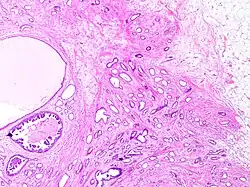

Tubular carcinoma

Histopathology of tubular carcinoma, low magnification, H&E stain. It shows the typical features of invasive breast cancer with infiltrative growth pattern, here including invasion into adipose tissue and with an associated fibrous or desmoplastic stromal response. It has the criterion of more than 90% of the tumor composed of small, ovoid or angulated tubules with open lumina. Ductal carcinoma in situ is seen at left as lumina with micropapillary formations (under the larger bland cyst), and was presumably the precursor lesion for the ductal carcinoma.[1]